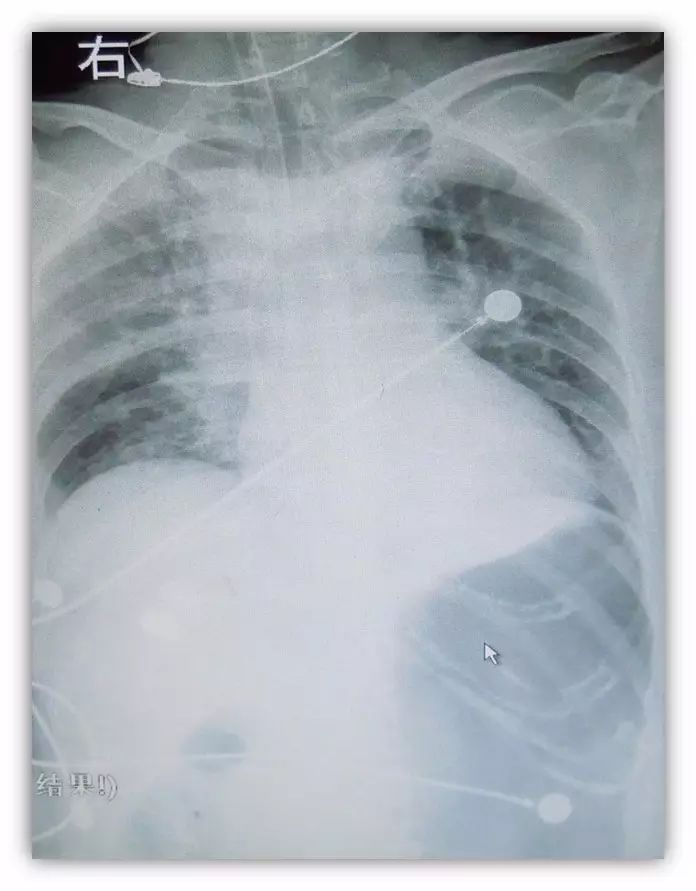

5.心肺复苏术后

无心律失常发作,但持续高热40.5°,点头样呼吸,饱和度低,无尿

SIMV,PC/PEEP20/10cmH2O, F16次/分,FiO2:100%, T39℃,BP80/40mmHg(股动脉),P80-118bpm SPO2 85-88%, RLS8级,双瞳等大同圆,双无干湿罗音,无哮鸣音,心率80-118次/分。腹-,四肢无自主活动,四肢指端肿胀明显。